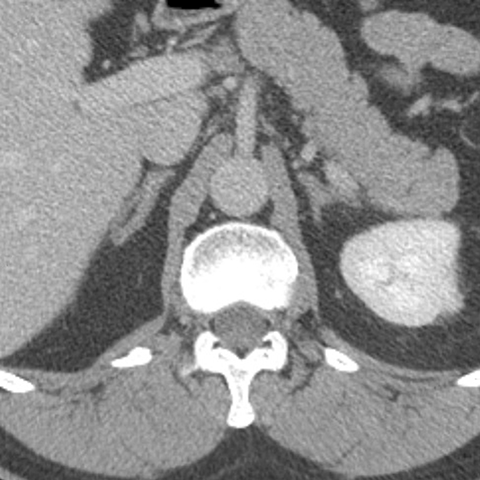

Normal Adrenal glands, CT [2 of 3]